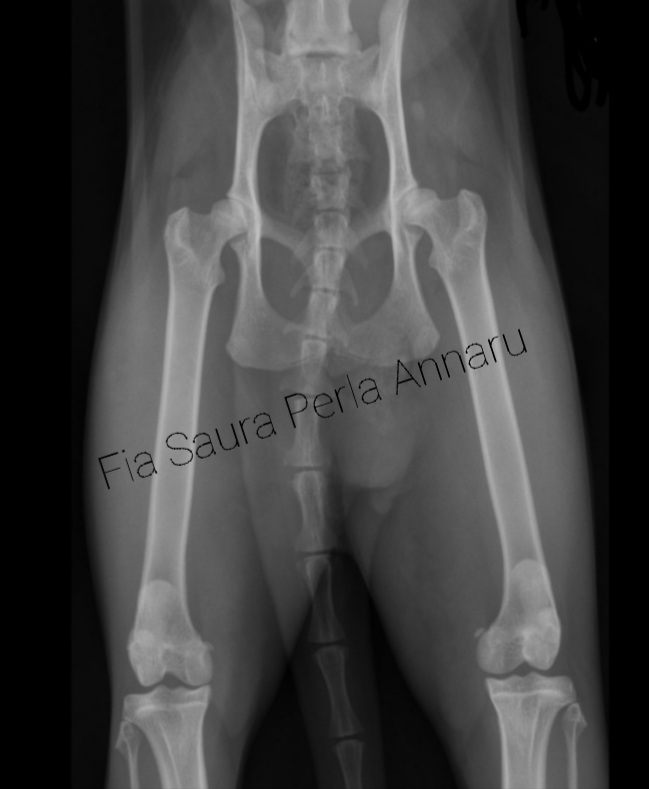

Fia Saura screen PL - HD

Afbeelding – 64,3 KB 374 downloads